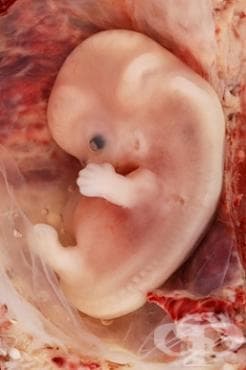

Как се развива бебето: през втория лунарен месец на бременността настъпват сериозни промени, като е налице преминаване от бластоцист към ембрион и стартиране на изключително бързо развитие на ембриона. През 5-та седмица се различават чертите на лицето, очите, ушите и започват да се оформят горните и долните крайници, които приличат на малки израстъци.

Този месец е важен за формиране на органите на плода. Вторият месец на бременността е критичен месец в неговото развитие. Той е част от ембрионалния период или периодът на органогенеза. Изключително важен момент в развитието на ембриона е периодът между 17-я и 56-я ден на бременността, тъй като тогава е най-податлив на фактори, които могат да попречат на нормалния му растеж.

През първите пет седмици от бременността се оформя невралната тръба на ембриона, от която се развиват мозъкът и гръбначният стълб. До края на втория месец сърдечната дейност може да бъде регистрирана на ултразвук. През седмата седмица на бременността ембрионът е с дължина 7-8 мм и тежи около 0.8 грама. Може да се видят ръцете, краката, очите, ушите и устата му. Сърцето, мозъкът, гръбначният мозък, мускулите и костите започват да се развиват. Плацентата, която ще участва в изхранването му, както и амниотичният сак, който осигурява топла и безопасна околна среда за плода, все още се формират.